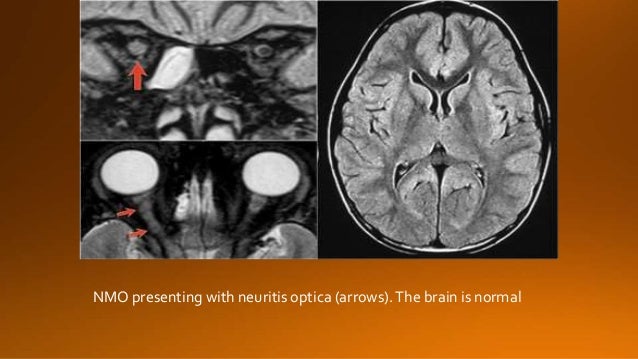

17. 17. NMO presenting with neuritis optica (arrows).The brain is normal

18. 18. One month later this child presented with acute transverse myelopathy, i.e. bilateral symptoms. The images show abnormal signal in the spinal cord with swelling and some enhancement. An astrocytoma could very well present with these images, but given the history of an optic neuritis and the acute myelopathy, we do not think of a tumor. This proved to be NMO and the Ig-test for NMO was positive.

19. 19. Previously it was thought that in NMO the brain was spared, but now we know, that brain lesions do occur. They are often distinct from those seen in MS. The location of the brain lesions in NMO is only around the ventricles.

20. 20. It is also possible to have large lesions in the corpus callosum of patients with NMO . So in any CNS disease with optic nerve and spinal cord involvement it is good to do the test for NMO-IgG.